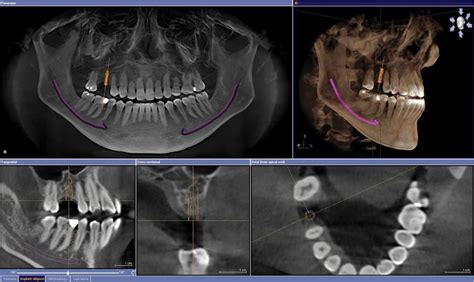

La creciente complejidad de las técnicas dentales ha conllevado un aumento paralelo en la demanda de precisión diagnóstica. El desarrollo de la implantología dental ha hecho de la tomografía computerizada (TC) una herramienta de primer orden en la planificación del tratamiento. Nuestro objetivo es exponer las capacidades y características de la imagen de TC a la hora de tomar decisiones informadas e integrar así esta técnica en sus prácticas. Los profesionales dentales deben conocer las posibilidades de la TC al hacer sus solicitudes.

El desarrollo de programas informáticos específicos ha propiciado la creciente utilización de la TC en el campo de la Odontología. Nuestro objetivo es familiarizar a los profesionales dentales con las capacidades de imagen de la TC para mejorar su toma de decisiones, permitiéndole integrar este procedimiento dentro de su proceso diagnóstico.

Entre las distintas técnicas de diagnóstico mediante imagen empleadas en odontología, la TC es el único método que permite valorar adecuadamente el hueso y no provoca distorsiones geométricas. Sin embargo, y aunque hay autores que la señalan como el método ideal para la planificación preimplantológica e incluso en el resto de patologías cuando la ortopantomografía no sea concluyente, aún hay ciertas discrepancias respecto a su uso rutinario en la implantología dental por el efecto adverso que supone la radiación recibida por el paciente.

Los cortes en este plano sagital mostrarían tan solo una parte de la anatomía dental pero son útiles para valorar el recorrido del conducto óseo del nervio alvéolo-dentario inferior o parte de los senos paranasales. Otra ventaja de la TC radica en que con una única exploración podemos realizar todas las reconstrucciones que queramos. De esta manera, podríamos reconstruir la mandíbula por una línea curva que siguiera su forma semicircular, obteniendo una imagen análoga a la ortopantomografía convencional.

Para comprender mejor las diferencias de información que obtenemos, iremos mostrando las imágenes que se pueden obtener de una mandíbula totalmente desdentada según la forma de reconstrucción.